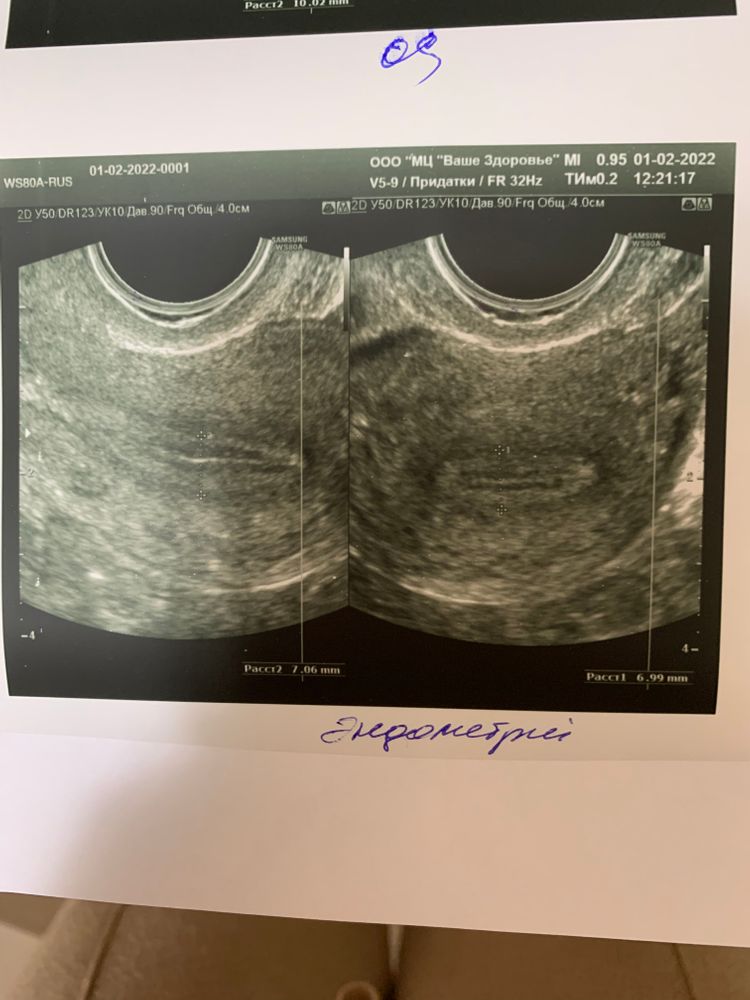

Эндик отличный вообще в этом цикле, уже 7 мм ))